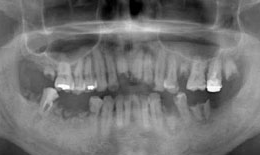

インプラント症例(20) 52歳 男性

治療前

下顎

保存困難な歯を抜歯後、インプラントを4本埋め込んで、セラミックスクラウンを被せた